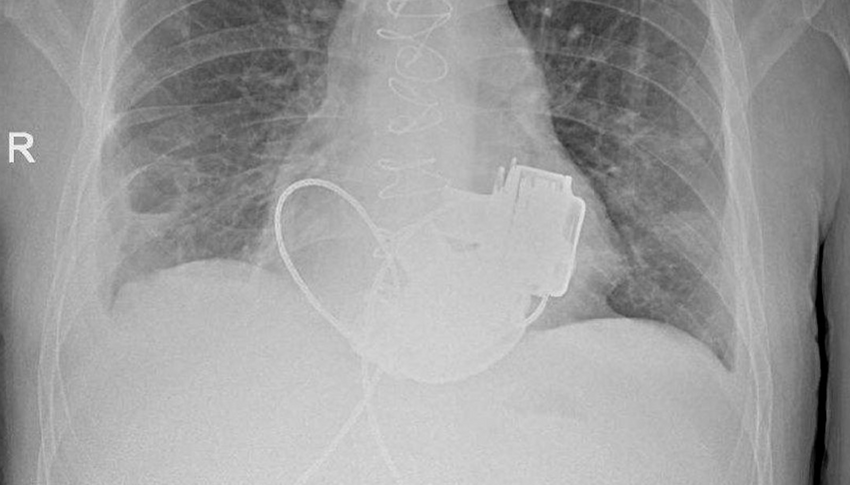

Ради спасения жизни парня целая бригада хирургов занялась им и провела крайне сложную операцию по имплантации двух искусственных желудочков. Теперь у Антона невозможно измерить пульс или давление, поскольку импланты создают только непульсирующий кровоток. Каждые 17 часов мужчина должен заряжать обновленное механическое сердце от двух аккумуляторов.